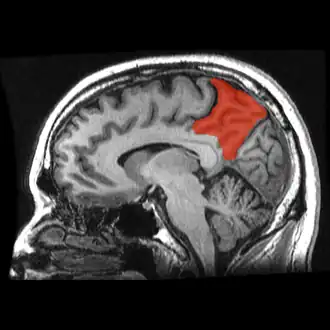

Precuneus

![]() Sagittal MRI slice with the precuneus shown in red. (Anterior to the left.) | |

In neuroanatomy, the precuneus is the portion of the superior parietal lobule on the medial surface of each brain hemisphere. It is located in front of the cuneus (the upper portion of the occipital lobe). The precuneus is bounded in front by the marginal branch of the cingulate sulcus, at the rear by the parieto-occipital sulcus, and underneath by the subparietal sulcus. It is involved with episodic memory, visuospatial processing, reflections upon self, and aspects of consciousness.

The precuneus is located on the inside between the two cerebral hemispheres in the rear region between the somatosensory cortex and forward of the cuneus (which contains the visual cortex). It is above the posterior cingulate. Following Korbinian Brodmann it has traditionally been considered a homogeneous structure and with limited distinction between it and the neighboring posterior cingulate area. Brodmann mapped it as the medial continuation of lateral parietal area 7.